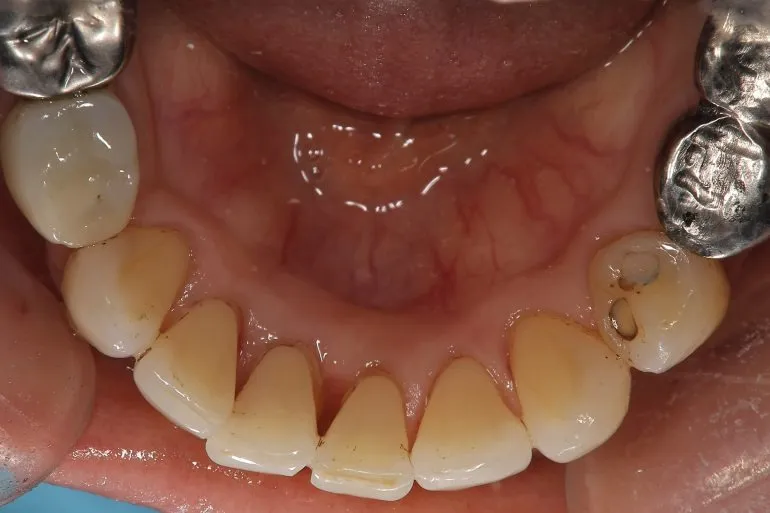

以下の茶色の着色がステインです!

当院のEMSというパウダーメンテナンスだとこれくらいにはキレイに落とせます🤗